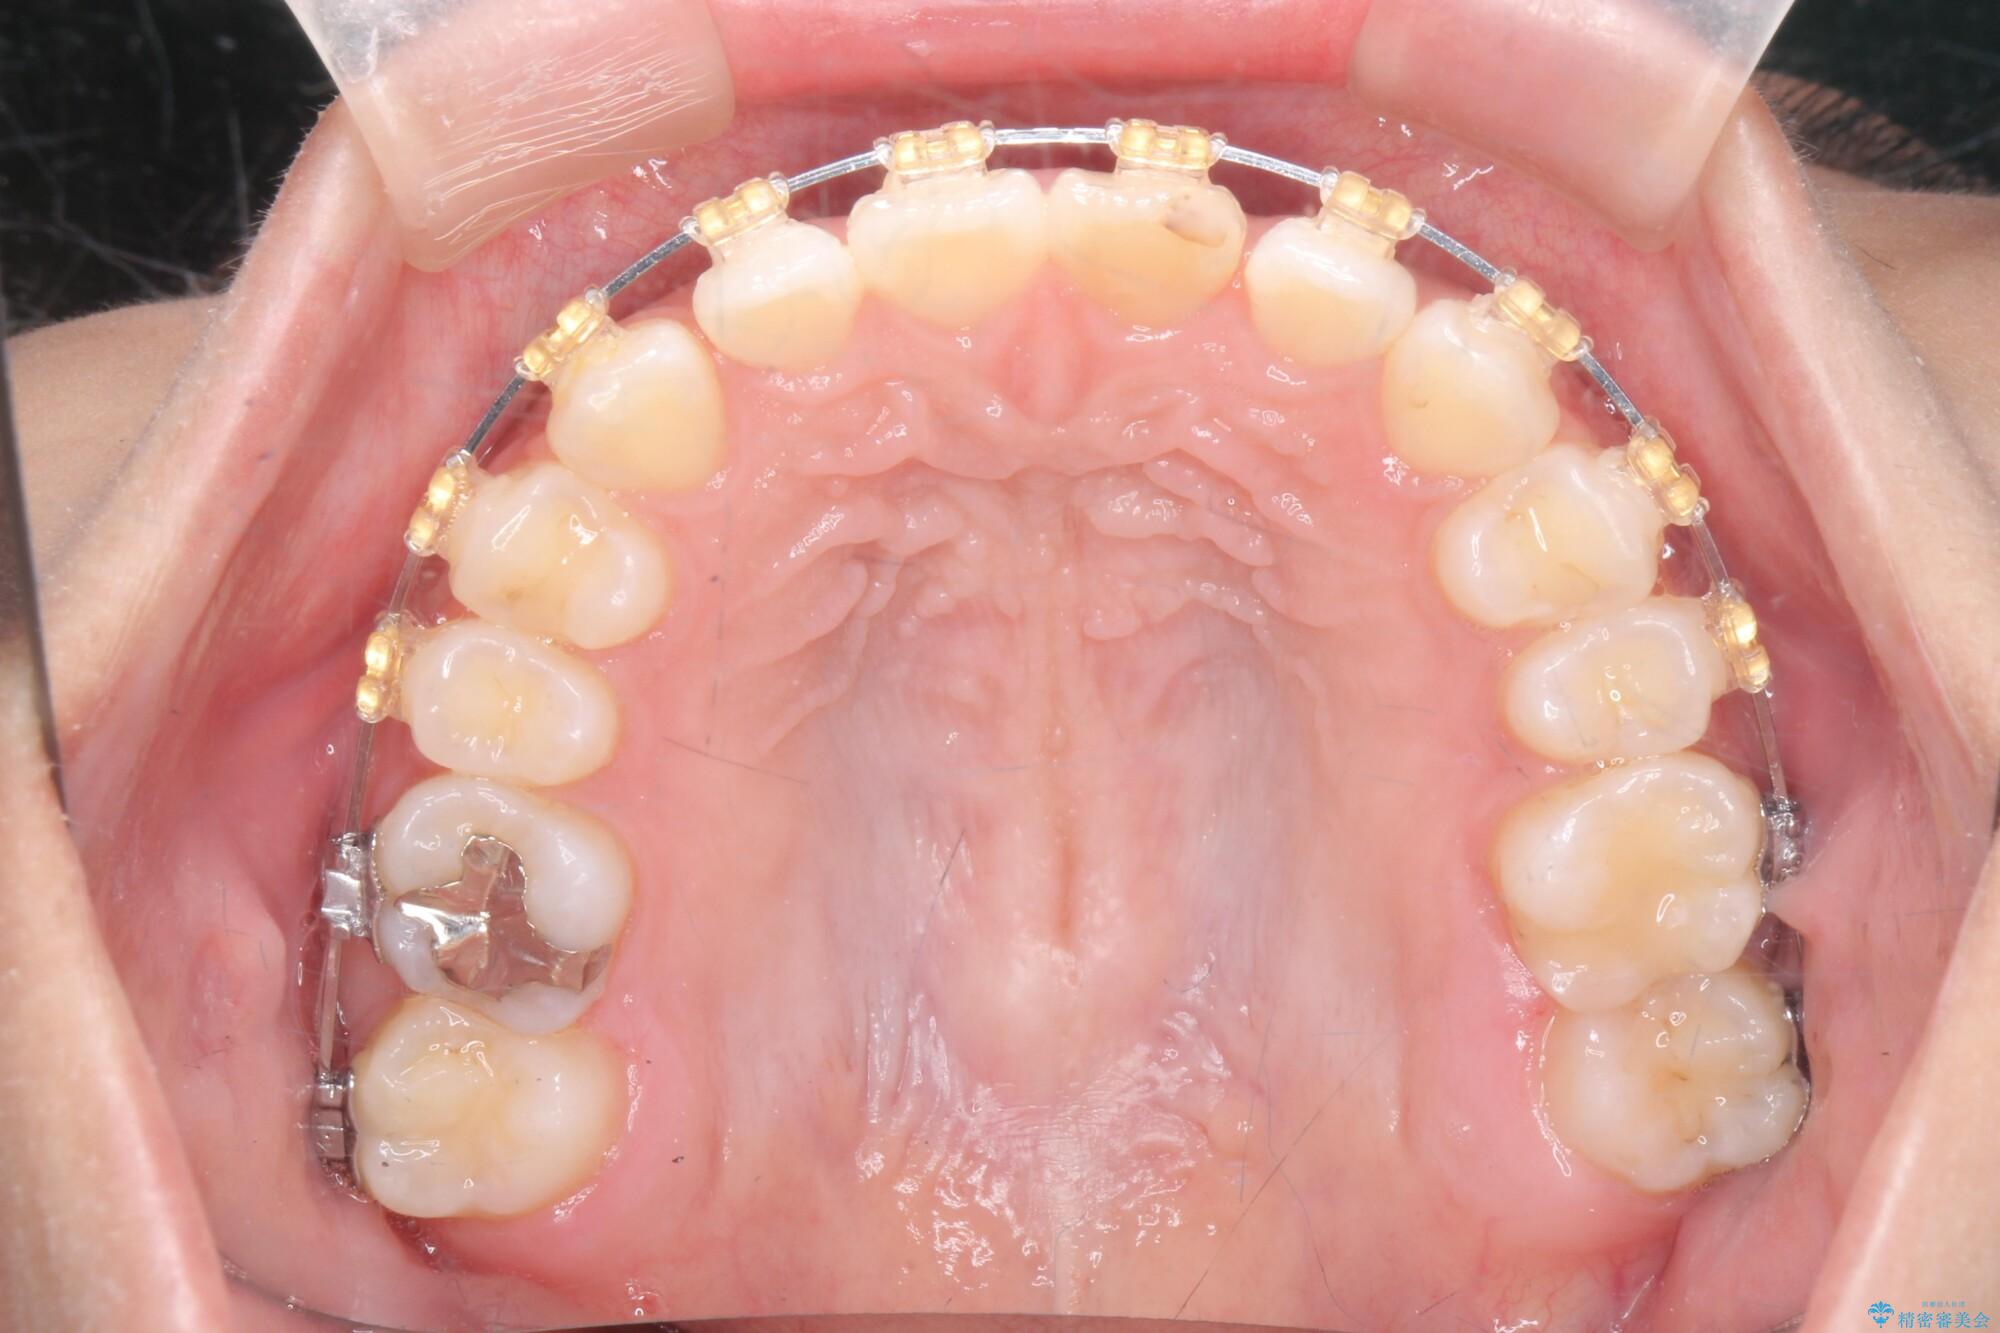

噛まない前歯と捻じれてしまった歯を改善したいと、矯正治療を希望された患者様です。

仕上がりにこだわりたいと、装置はマウスピースではなくワイヤーを希望されました。

マルチブラケットを用いた非抜歯のワイヤー矯正で噛み合わせと歯並びを改善していきます。